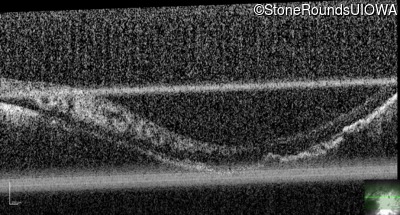

Optical Coherence Tomography - Right - 20/200 -1

Exemplar / OCT Stack